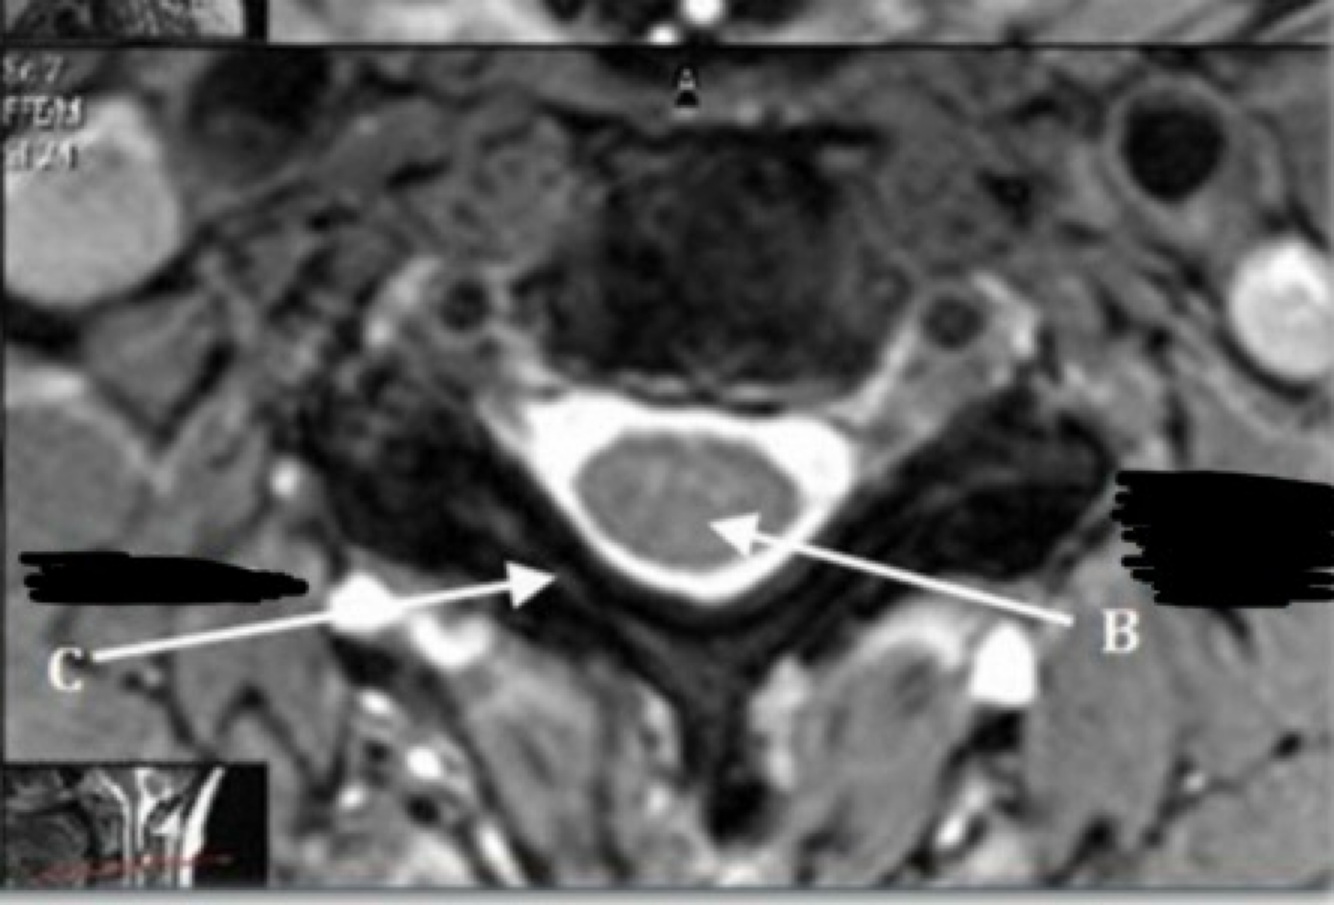

45

What is letter A?

L4-5 INTERVERTEBRAL DISK SPACE

46

What is letter B?

PEDICLE

47

What is letter C?

NERVE ROOTS

48

What is letter D?

CSF

49

What is letter E?

ERECTOR SPINAE MUSCLE

50

What is letter F?

FACET (ZYGAPOPHYSEAL) JOINT

51

What is letter G?

L5 VERTEBRAL BODY

52

What is letter H?

SPINOUS PROCESS

53

What is letter J?

LAMINA

54

What is letter K?

PSOAS MUSCLE